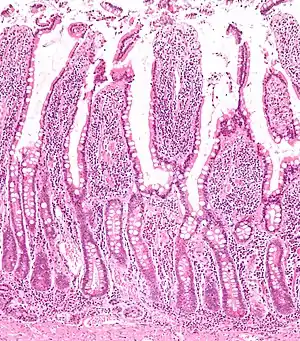

Micrograph of the small intestine mucosa showing the intestinal villi and crypts of Lieberkühn.

The three sections of the small intestine look similar to each other at a microscopic level, but there are some important differences. The parts of the intestine are as follows:

Mucosa: intestinal epitheliumSimple columnar. Contains goblet cells, Paneth cellsSimilar to duodenum, but the intestinal villus is longSimilar to duodenum, but the intestinal villus is short